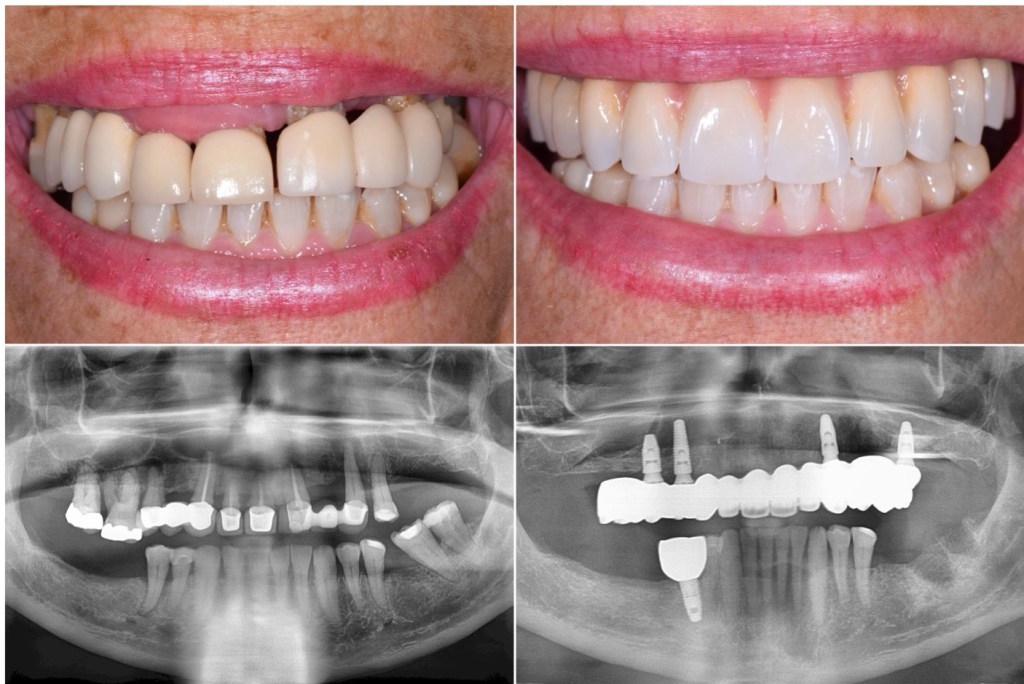

三、廣告只給你看「口外照」,卻不給你看「口內真相」

你在廣告中看到的術後照,幾乎都是:(以下照片取得:網路)

✅ 微笑

✅ 嘴唇閉合

✅ 看起來一整排白牙

但實際上,臨床上常見的口內問題包括:

• 🔸 金屬結構外露

• 🔸 牙縫過大、不自然

• 🔸 假牙形態厚重,一旦斷裂維修困難,幾乎需整組重換

• 🔸 食物卡縫、清潔困難

• 🔸 長期發炎與異味困擾

這些畫面,很少出現在廣告裡。

等到病人真的翻開嘴巴看到,往往已經來不及退換。